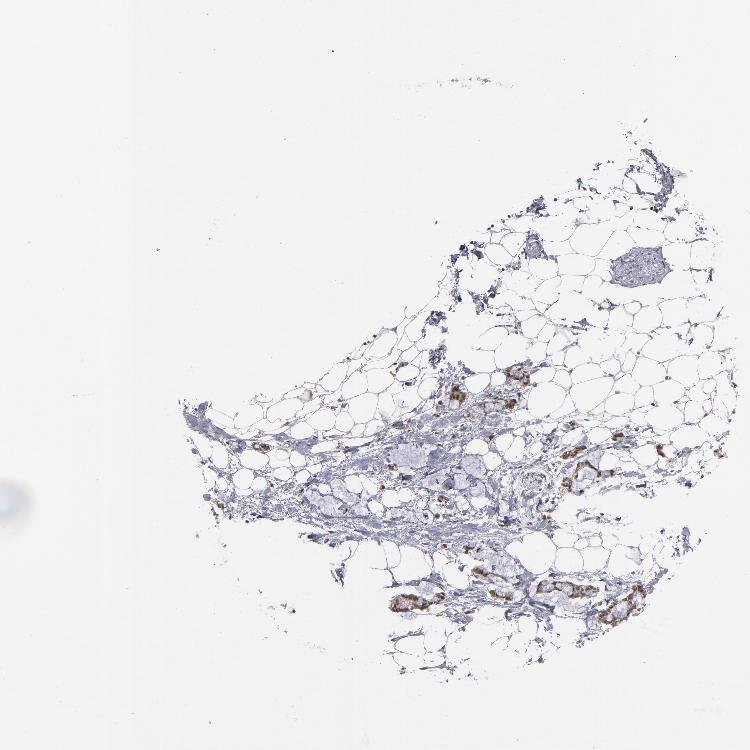

SOFT TISSUE 2 - Antibody stainingi

Antibody staining in the annotated cell types in the current human tissue is reported as not detected, low, medium, or high, based on conventional immunohistochemistry profiling in selected tissues. This score is based on the combination of the staining intensity and fraction of stained cells.

Each image is clickable and will lead to virtual microscopy that enables deeper exploration of all samples and also displays staining intensity scores, fraction scores and subcellular localization as well as patient and tissue information for each sample.

Antibody HPA001538Antibody CAB008632

Fibroblasts Not detectedNot detected

Peripheral nerve Not detected-